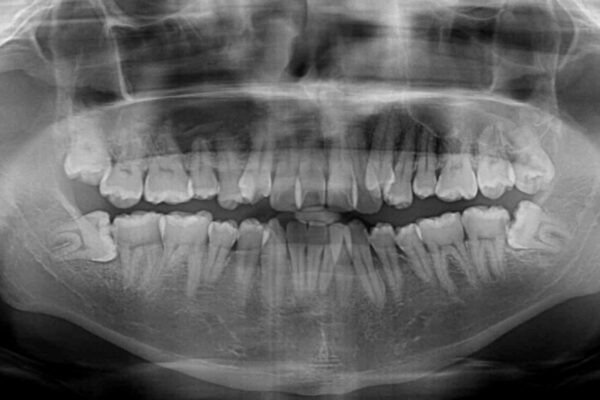

八重歯と前歯のクロスバイトを改善したいとのことで来院された患者様です。

デコボコの程度は強かったのですが、口元の突出感はなかったため、非抜歯矯正としました。

治療前

• 八重歯とクロスバイト 目立たないワイヤー装置で矯正治療 治療前画像